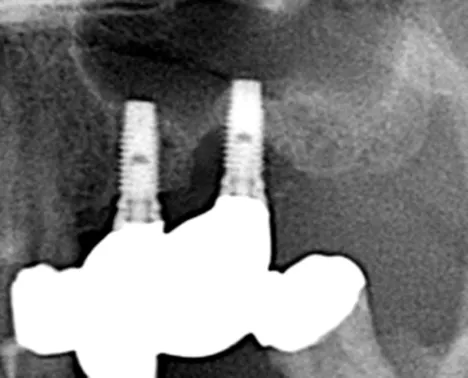

Dr.Tachikawa_Fig.1

Fig. 1. Panoramic X-ray image at onset of peri-implantitis.